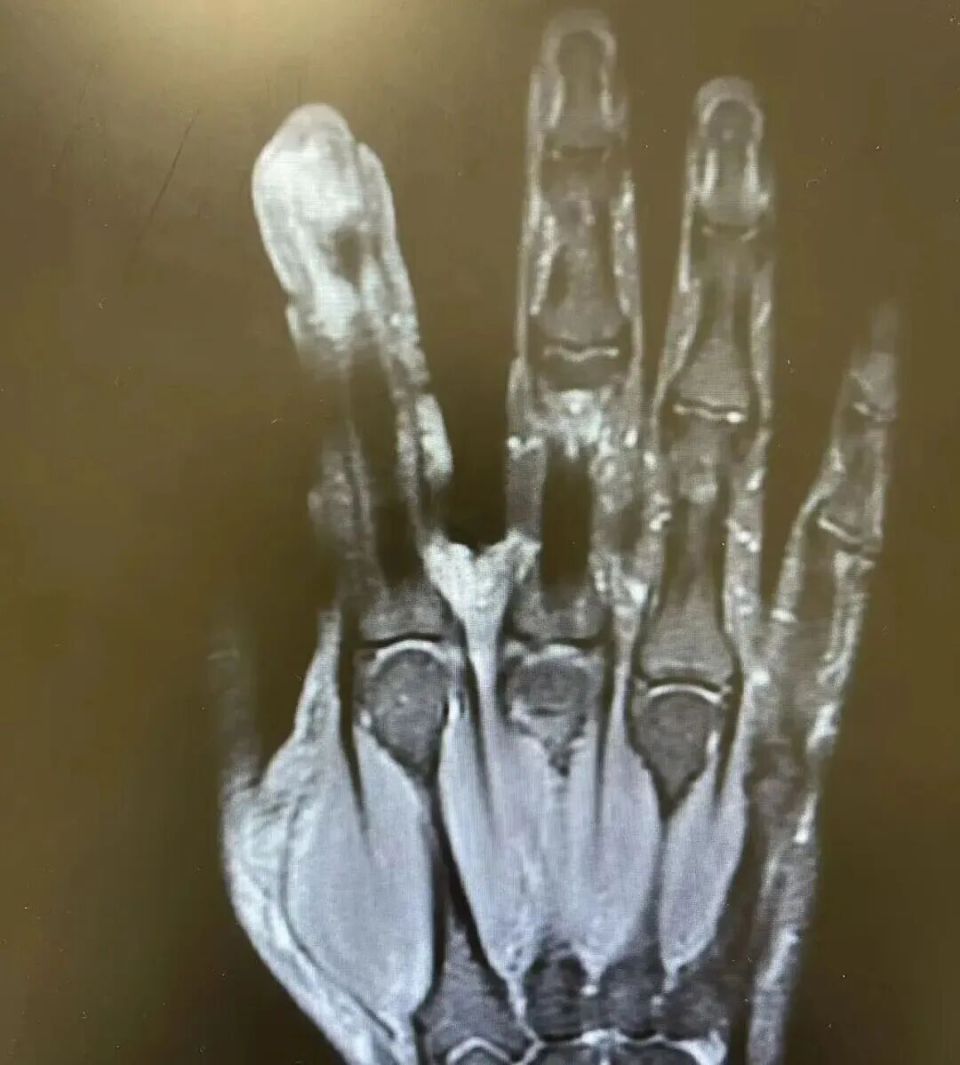

经检查,李先生破溃的左手指尖严重感染,厌氧消化链球菌顺着破损处钻到骨头里,引发了严重骨髓炎。医生紧急手术,帮其“刮掉”坏死的骨头碎片,清除了坏死的肌肉与皮肤。

图片